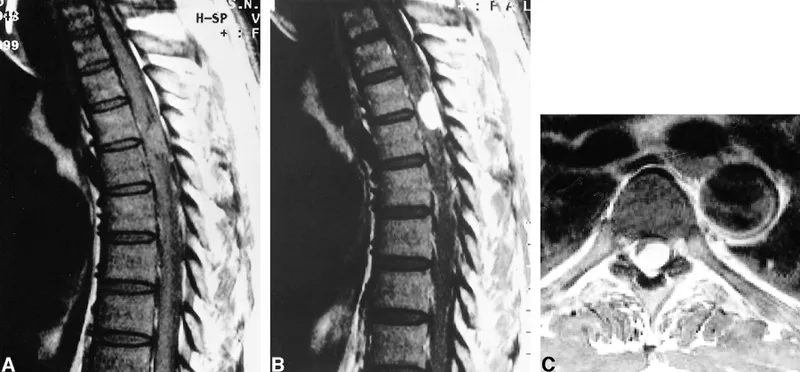

| Cauda Equina Syndrome (CES) | Bilateral sciatica, saddle anaesthesia, urinary retention/incontinence, fecal incontinence, progressive leg weakness | Emergency MRI <24h |

| Spinal Infection | Fever, IV drug use, immunosuppression, recent UTI/bacteremia, night sweats, TB risk factors | Urgent MRI + bloods |

| Malignancy | Age >50, unexplained weight loss, past cancer history, night pain, thoracic pain, progressive symptoms >4-6 weeks | Urgent MRI ± XR |